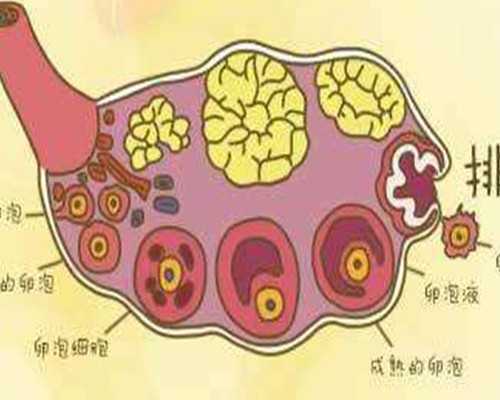

促排卵過程不同

不管是人工授精還是試管嬰兒,他們的促排卵的過程多多少少的都會有所不同,人工授精是可以促排卵,也可以自然來進行排卵,而食管嬰兒必須要選擇超出排卵,也就是說他們在做試管嬰兒的過程當中會一次性提取20多個卵子,這樣的話才能夠配置成各種不同的胚胎,從而在無形當中增加試管嬰兒成功率,有效降低試管嬰兒費用。一次性的促排卵費用,可能價格也在1萬元到2萬元之間。